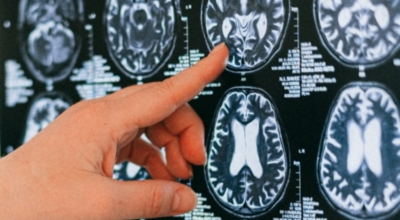

뇌종양이란 뇌 조직이나 뇌를 싸고 있는 막에서 발생한 종양과, 머리뼈나 주변 구조물로부터 멀리 떨어진 부위에서 뇌 조직이나 뇌막으로 전이된 종양을 의미해요. 뇌종양은 양성과 악성으로 나눌 수 있습니다. 양성 뇌종양은 성장 속도가 느리며 주위 조직과의 경계가 뚜렷해요. 양성 뇌종양은 수술 이외의 다른 치료 없이 완치되는 경우가 흔하고, 대부분 천천히 자라기 때문에 수술하지 않고 경과를 관찰하기도 해요. 그러나 양성 뇌종양도 완치될 수 없는 경우가 있습니다.

뇌간이나 척수와 같은 특정 부위에 발생된 종양은 수술로 없앨 수 없습니다. 또 크기가 작더라도 생명에 중요시되는 기능을 담당하는 뇌와 척수에 정도가 심한 훼손을 입힐 수 있답니다. 이 경우 조직학적으로는 양성이지만, 임상적으로는 악성과 같습니다. 악성 뇌종양은 뇌암이라고도 하고, 성장 속도가 빠르며 주위 조직으로의 침투 역량이 강해요. 이에 따라 정상 뇌 조직으로 침윤되고 정상 뇌 조직과의 경계가 불분명해서 치료가 어려운 편이예요. 악성 뇌종양은 주변의 정상 뇌 조직을 빠른 속도로 파괴해요.